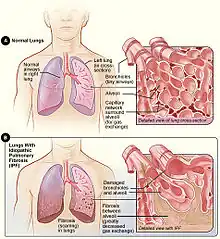

| Figure A shows the location of the lungs and airways in the body. The inset image shows a detailed view of the lung's airways and air sacs in cross-section. Figure B shows fibrosis (scarring) in the lungs. The inset image shows a detailed view of the fibrosis and how it damages the airways and air sacs.[1] | |

Idiopathic pulmonary fibrosis (IPF), or (formerly[5]) fibrosing alveolitis, is a rare, progressive illness of the respiratory system, characterized by the thickening and stiffening of lung tissue, associated with the formation of scar tissue. It is a type of chronic scarring lung disease characterized by a progressive and irreversible decline in lung function.[3][4] The tissue in the lungs becomes thick and stiff, which affects the tissue that surrounds the air sacs in the lungs.[6] Symptoms typically include gradual onset of shortness of breath and a dry cough.[1] Other changes may include feeling tired, and abnormally large and dome shaped finger and toenails (nail clubbing).[1] Complications may include pulmonary hypertension, heart failure, pneumonia or pulmonary embolism.[1]

The cause is unknown, hence the term idiopathic.[2] Risk factors include cigarette smoking, acid reflux disease (GERD), certain viral infections, and genetic predisposition.[1] The underlying mechanism involves scarring of the lungs.[1] Diagnosis requires ruling out other potential causes.[3] It may be supported by a HRCT scan or lung biopsy which show usual interstitial pneumonia (UIP).[3] It is a type of interstitial lung disease (ILD).[3]